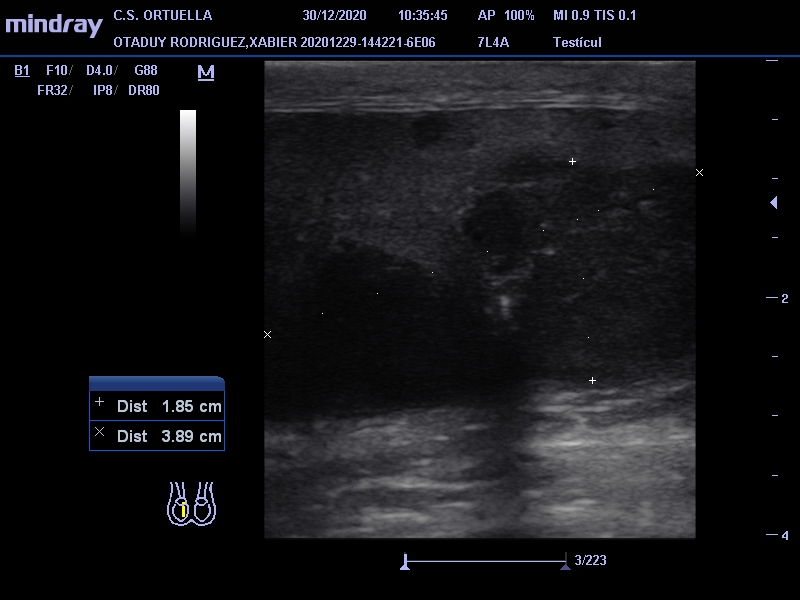

Hallazgos ecográficos

Masa de 38 x 40 mm, hipoecogénica, con aumento de vascularización mediante doppler, en polo inferior de teste derecho.